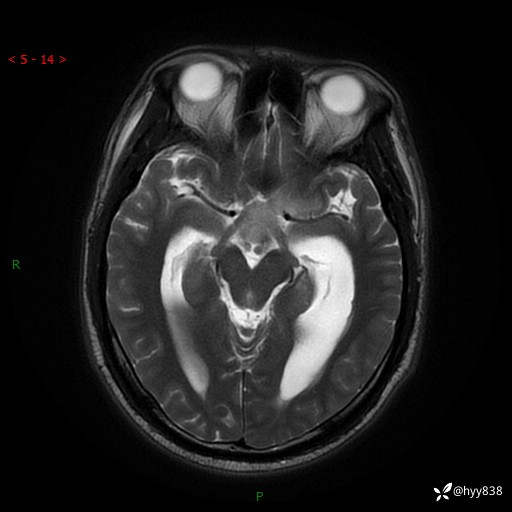

颅脑MRI平扫+增强